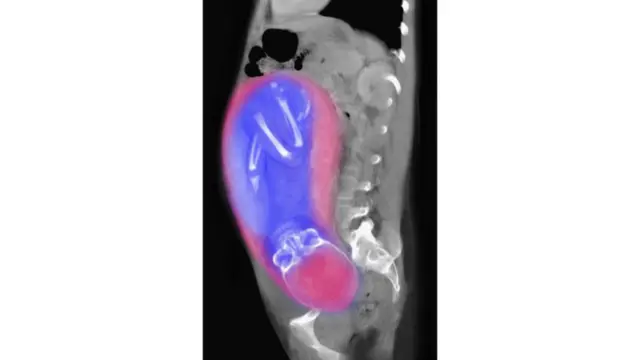

Penelitian pada Mei 2016 yang dipimpin oleh Marcia Ponce de León dan Christoph Zollikofer di University of Zurich, Swiss meneliti data panggul dari 275 orang — laki-laki dan perempuan — dari segala umur. Peneliti menyimpulkan bahwa panggul berubah dimensinya sepanjang hidup perempuan.

Data mereka menunjukkan kemungkinan bahwa panggul perempuan mengambil bentuk yang mendukung proses kelahiran pada masa akhir remaja — saat dia mencapai tingkat kesuburan tertingginya. Panggul berada dalam bentuk itu sampai sekitar usia 40 tahun dan kemudian berubah bentuk menjadi kurang mendukung kelahiran, dan siap untuk menopause.

Ilmuwan mengatakan bahwa perubahan-perubahan ini membuat proses kelahiran sedikit lebih mudah daripada yang mungkin terjadi. Mereka menyebut teori ini "dilema obstetrik pertumbuhan" (DOD).

"Hipotesis DOD memberikan penjelasan pertumbuhan dalam variasi dimensi panggul obstetris," kata Ponce de León.